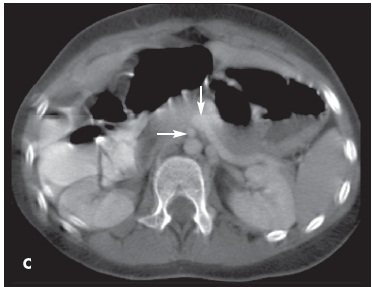

Ronald Swanger, MD; Adele Brudnicki, MD

<P><IMG style="MARGIN: 5px; FLOAT: left" alt="Appendicitis With Intestinal Malrotation" src="/sites/default/files/transfer/0801cfpPCAppC_thumb.jpg" width=90...